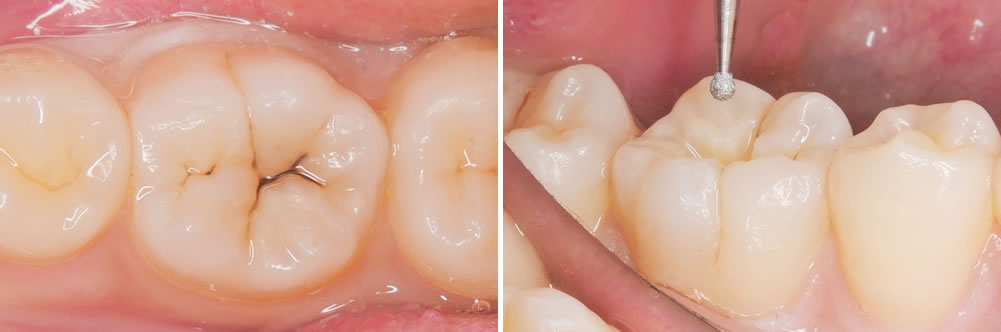

こちらの患者さまは、右下奥歯の虫歯を主訴に来院されました。

右下の奥歯に黒い部分が見受けられます。範囲は小さいため、出来るだけ削らないように先端の小さな器具を用いて丁寧に虫歯を除去していきます。

虫歯治療の除去

う蝕検知液を用いて丁寧に虫歯を取り除いていきます。

さらに奥にある虫歯は、より小さな器具を用いて削る範囲が大きくなりすぎないようにします。